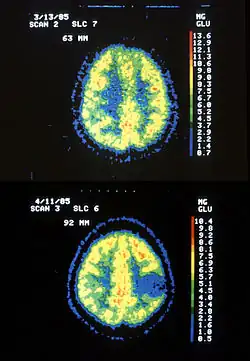

Two PET images—the upper of which shows a normal brain and the lower shows astrocytoma

Astrocytoma is a type of brain tumor. Astrocytomas (also astrocytomata) originate from a specific kind of star-shaped glial cell in the cerebrum called an astrocyte. This type of tumor does not usually spread outside the brain and spinal cord, and it does not usually affect other organs. After glioblastomas, astrocytomas are the second most common glioma and can occur in most parts of the brain and occasionally in the spinal cord.[1]